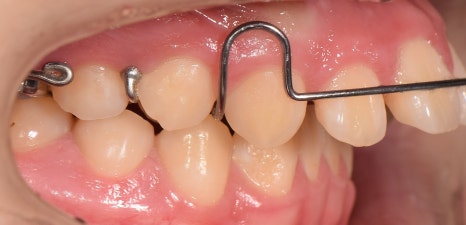

교정의 한 분야인,

헤드기어 =head gear는

1) 입안에 끼는 장치

2) 머리에 쓰는 밴드

3) 이들을 연결하는 탄성 모듈로 구성되어 있으며,

위 사진처럼,

위턱뼈가 앞으로 돌출되었을 때

상악 성장을 막기 위해 사용되고 있습니다.

즉, 위턱뼈가

앞으로 자라지 못하도록

뒤로 당겨주는 역할을 하게 되는데요.

가철식 장치 및 헤드기어 착용